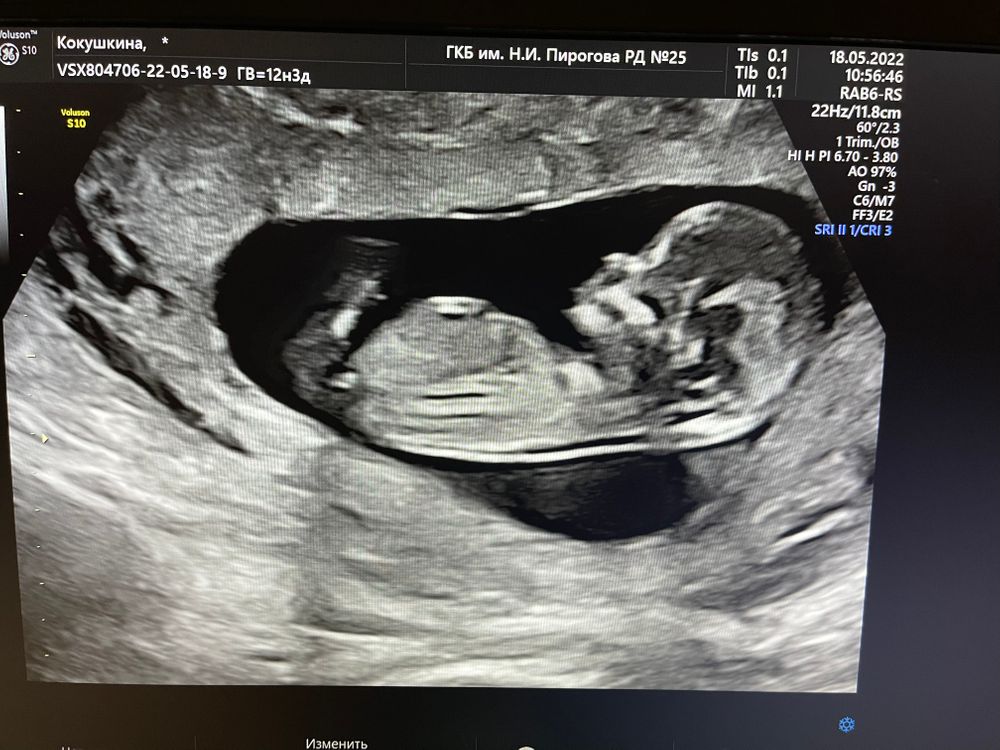

Поздравляю вас!!! 💐 У нас на 1 скрининге почти такой же бугорок как у вас, в 12 нед 1д. Вы вселели в меня надежду, что есть шанс на мальчика😄

На первом и правда не видно половой бугорок.

Поздравляюююю😍😍😍🌸🌸🌸 это уже 3 пост, где пишут, что по первому скринингу возможно девочка, по второму уже точно мальчик😂 у меня тоже так получилось🤗🤗🤗